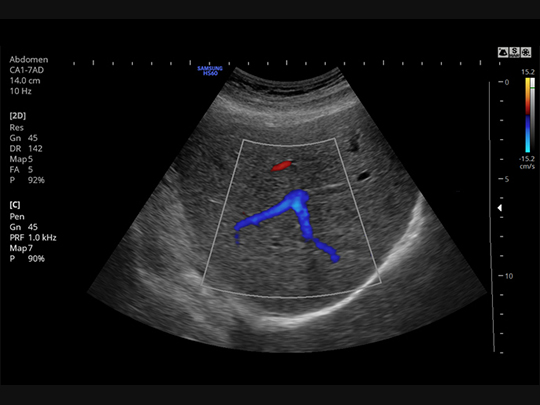

S-Flow™

A sophisticated color Doppler technology with greater sensitivity, S-Flow can detect low-intensity blood flow. It enables accurate diagnosis when blood flow examination is especially difficult.

Samsung HS60 Compatible Transducers / Probes

Curved array transducers

CA1-7AD

- Application: abdomen, obstetrics, gynecology